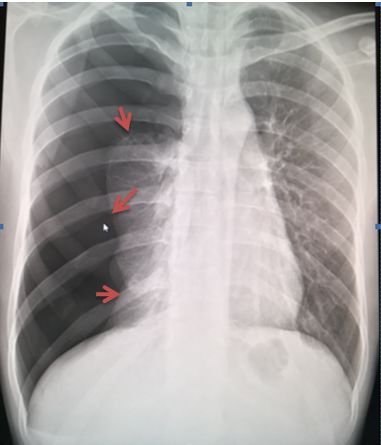

病例5

病例5患者左肺野外带可见无血管纹理区及肺叶压缩带边缘(红色箭头),肺叶压缩约5%

点拨:有时肺组织压缩边缘全部或部分与肋骨走行重合,可以通过调节负相帮助进一步观察。